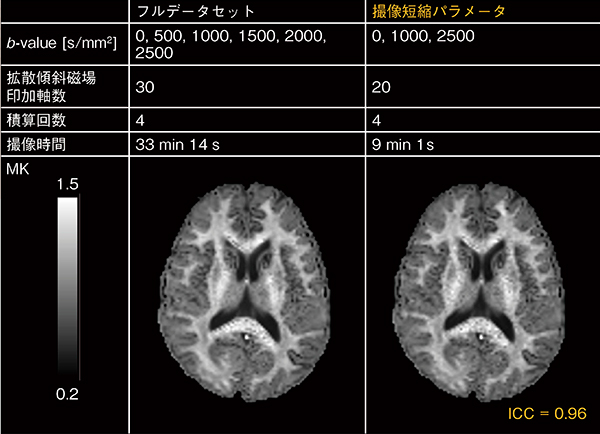

日立では,計測精度を維持しながら計測時間を短縮するために,計測パラメータの最適化を行っています3)。計測精度は,特にb-vectorの絶対値や印加軸など,拡散強調にかかわる計測パラメータの選択に大きく依存しています。このため,これら計測パラメータの最適値を,1.5T MRIを用いて実測により検討しました。b-vectorの絶対値を6点,印加軸を30軸,積算回数を4回としたフルデータセットを計測し,本データセットからさまざまな組み合わせで選択したサブデータセットを生成しました。フルデータセットで計算した指標MK,K∥,K⊥を参照指標とし,各サブデータセットで計算した指標との間でIntraclass Correlation Coefficient(ICC:級内相関係数)を評価し,ICCの高い最適なサブセットを探索しました。

この結果,b-vectorの絶対値は0,1000,2500s/mm2の3点,印加軸は20軸の撮像時間短縮パラメータで,フルデータセットと同様な指標MKが得られることがわかりました(図4)。これにより,計測時間は約1/3.5に短縮可能となります。

図4 フルデータと撮像短縮パラメータで得られたデータによるDKI(MK)の比較

最適化した撮像短縮パラメータを使用することで,撮像時間を約1/3.5にしながら,Intraclass Correlation Coefficient(ICC)=0.96とフルデータセットとほぼ同等のMKマップが得られています。